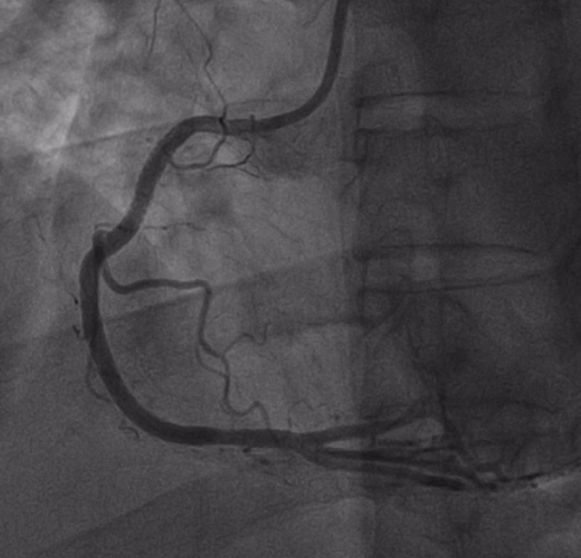

患者到达导管室后,张丙坤主任带领的介入团队立即为患者实施紧急介入治疗,并顺利开通血管,患者胸闷症状明显减轻。术后转入心血管内科二区病房继续治疗。

术前